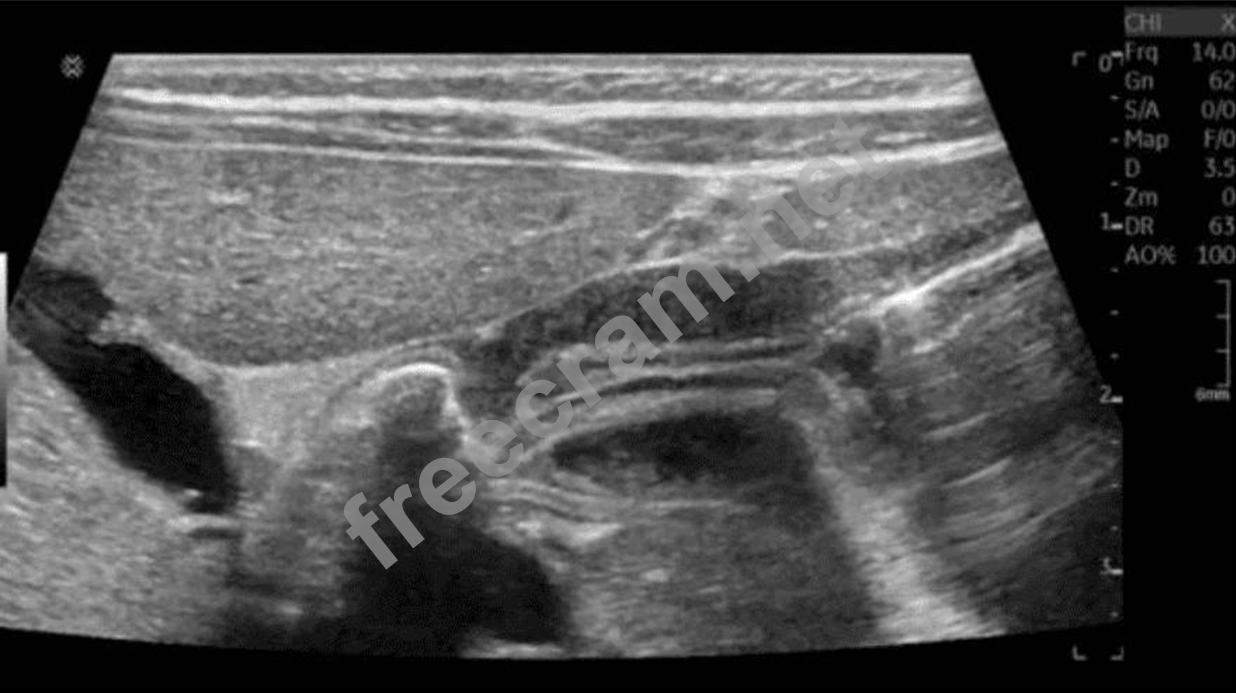

Which clinical finding is most likely associated with the pathology in this image?

Question 69: Which clinical finding is most likely associated with the pa...